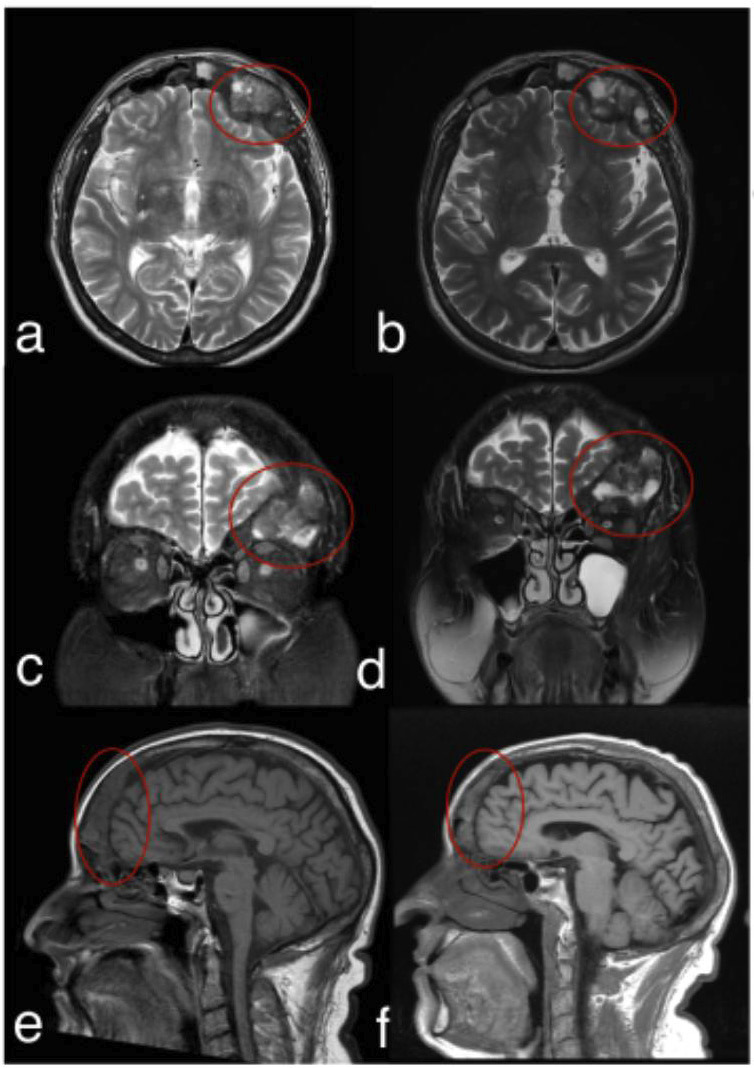

This case report describes a rare, asymptomatic brown tumor in a patient with end-stage renal disease. The lesion was incidentally detected during a computed tomography (CT) scan of the paranasal sinuses, performed upon a dentist's recommendation to investigate maxillary sinusitis. CT imaging revealed an expansive osteolytic lesion with irregular margins and a ground-glass appearance involving the left side of the sphenoid and frontal sinuses. Subsequent magnetic resonance imaging (MRI) with multiplanar T1 and T2-weighted sequences without contrast demonstrated a solid tissue-like expansive lesion affecting the left frontal and sphenoid bones, mildly compressing adjacent cerebral parenchyma. Despite these findings, the patient remained asymptomatic. Conservative management, including pharmacological therapy with calcimimetics to control parathyroid hormone levels, was initiated. A follow-up MRI after five years showed lesion stability without significant changes. The patient later underwent a renal transplant, which effectively stabilized the bone disease and improved his quality of life. This case underscores the pivotal role of computed tomography (CT) in detecting incidental systemic skeletal changes and the indispensable importance of interdisciplinary collaboration in managing complex conditions in systemically compromised patients, where each professional's expertise is crucial for the patient's well-being. Key words:Sinusitis, Brown Tumor, Hyperparathyroidism, Multidetector Computed Tomography, Magnetic Resonance Imaging, Multidisciplinary Care Teams.